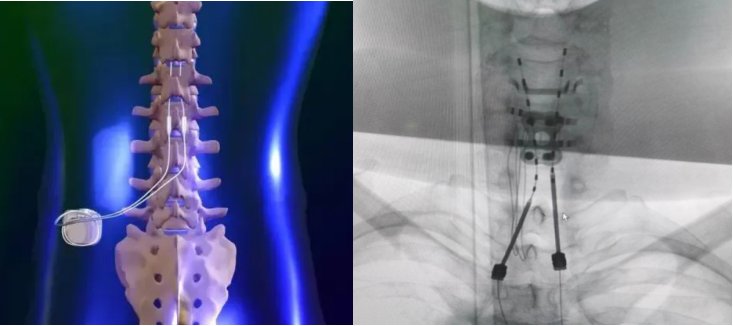

(三)脊髓电刺激术(SCS,Sacral Neuromodulation)

脊髓电刺激术的主要适应症:慢性疼痛、腰椎手术失败综合征、缺血性疼痛等(全球15亿人遭受慢性疼痛困扰)脊髓电刺激是将一根细电极植入置人脊髓背侧硬膜外腔,利用脉冲电流刺激脊髓神经以阻断疼痛信号传导的一种神经调控技术。它能减弱或增强从外周向中枢系统的神经冲动流,即刺激粗纤维,抑制细纤维痛觉信息的接收,从而达到缓解疼痛的效果。在SCS动物模型和众多患者中,都观察到血管舒张的现象,这种现象很可能继发于SCS缓解疼痛后的效果。

图:脊髓电刺激术示意图近30多年来,对该技术的病理生理、适应证、预期疗效及可能出现的并发症进行了大量的深入研究,SCS已成为当今临床疼痛领域里的一项重要镇痛技术。据2017年美国神经外科医师协会统计,目前在全球每年有5万以上病例进行脊髓电刺激治疗,总有效率约80%,但我国此项技术开展相对较少。传统SCS疗法对于背部术后疼痛综合征、复杂性区域疼痛综合征、痛性糖尿病周围神经病变的疗效已得到广泛认可,对周围神经损伤性疼痛、慢性顽固性心绞痛及周围血管病等亦有效,但尚缺乏相关大型、长期随访的临床研究提供高质量证据。传统SCS镇痛的确切机制至今尚未完全阐明,目前认为可能参与的机制有:①激活Aβ纤维、兴奋抑制性中间神经元进而关闭脊髓后角神经元的“疼痛闸门”;②调节抑制性神经递质γ-氨基丁酸(GABA)、乙酰胆碱(Ach)、5-羟色胺(5-HT)等的释放;③调节疼痛相关神经环路;④神经功能的重塑作用等。